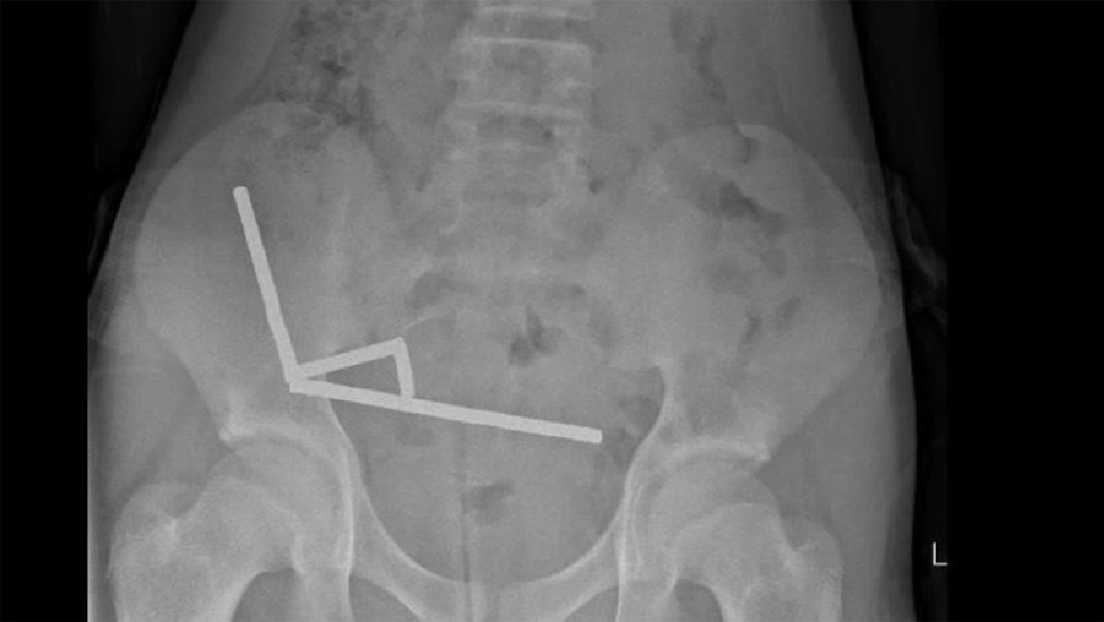

El adolescente acudió al hospital con dolor abdominal y admitió haber ingerido una gran cantidad de imanes de neodimio aproximadamente una semana antes. Mediante una radiografía, los médicos visualizaron cuatro cadenas lineales en diferentes partes del intestino del paciente. Una vez dentro, los pequeños objetos metálicos se unieron de forma destructiva.

Durante la intervención quirúrgica, se encontraron las cadenas en secciones separadas del intestino delgado y el ciego. Al apretarse, causaban la muerte de varias áreas de tejido por falta de sangre, lo que se conoce como necrosis por presión.